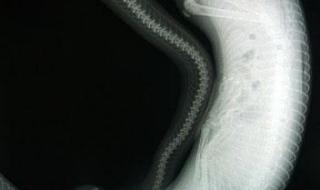

2、比如网上传的北京动物园百米巨蟒事件,就是假的。还有网传的四川地震惊现55米巨蟒,也是假的。 所以所谓的北京动物园百米巨蟒事件是假的,以及四川55米巨蟒和15米长的“桂花”都是假的,虽然我不敢说这世界上一定没有百米、50米的巨蟒,但网传的北京动物园百米巨蟒以及四川的55米巨蟒肯定都是假的!